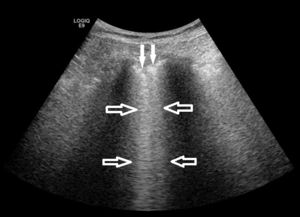

Imagen ecográfica del pulmón en una paciente con EPID. Se detectan los artefactos denominados líneas B (flechas huecas) y un engrosamiento irregular de la pleura (flechas sólidas), ambos hallazgos indicativos de las alteraciones alvéolo-intersticiales y pleurales que se producen en las EPIS.